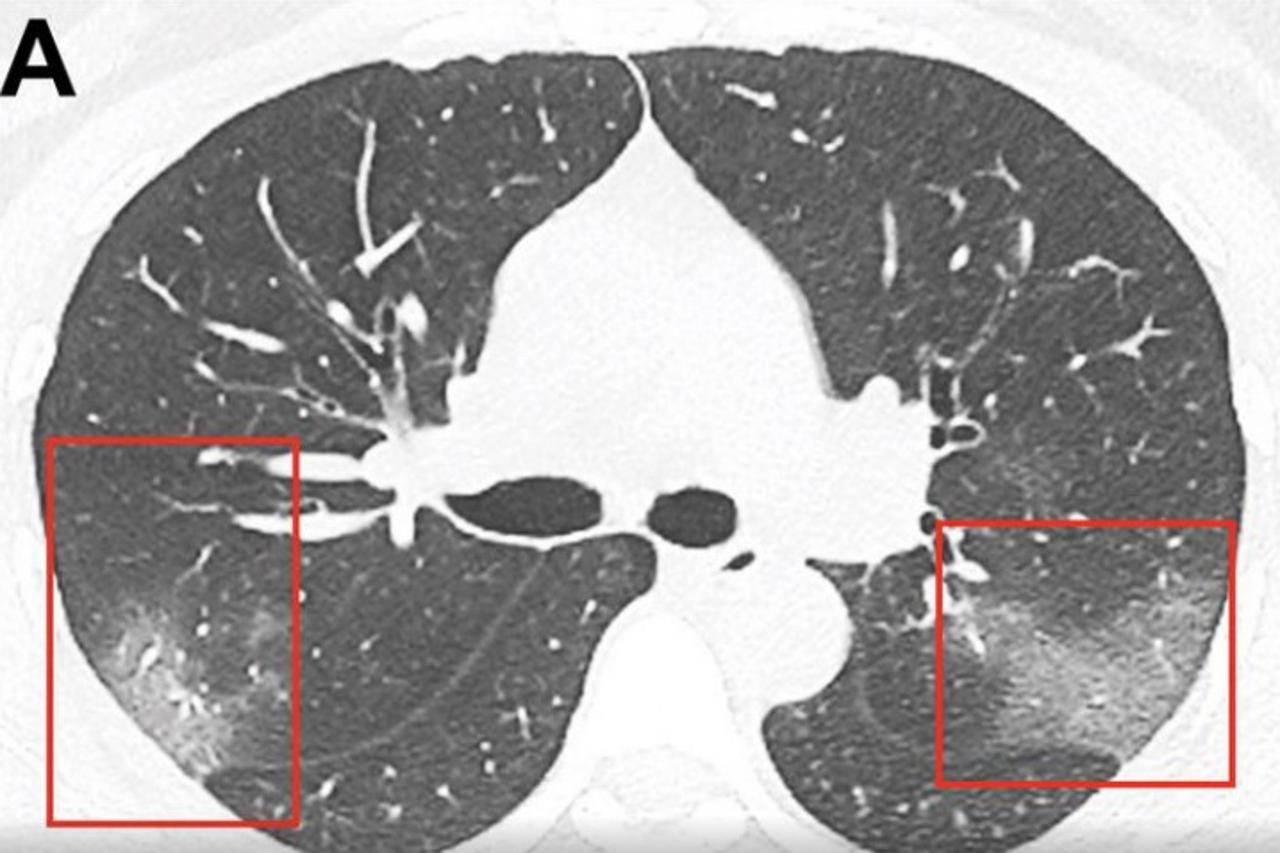

koronavirus

Stručnjaci imaju teoriju o novim virusima. Je li koronavirus 'bolest X' - prijetnja čovječanstvu

U 15 godina koronavirus uzrokovoa tri globalne epidemije.